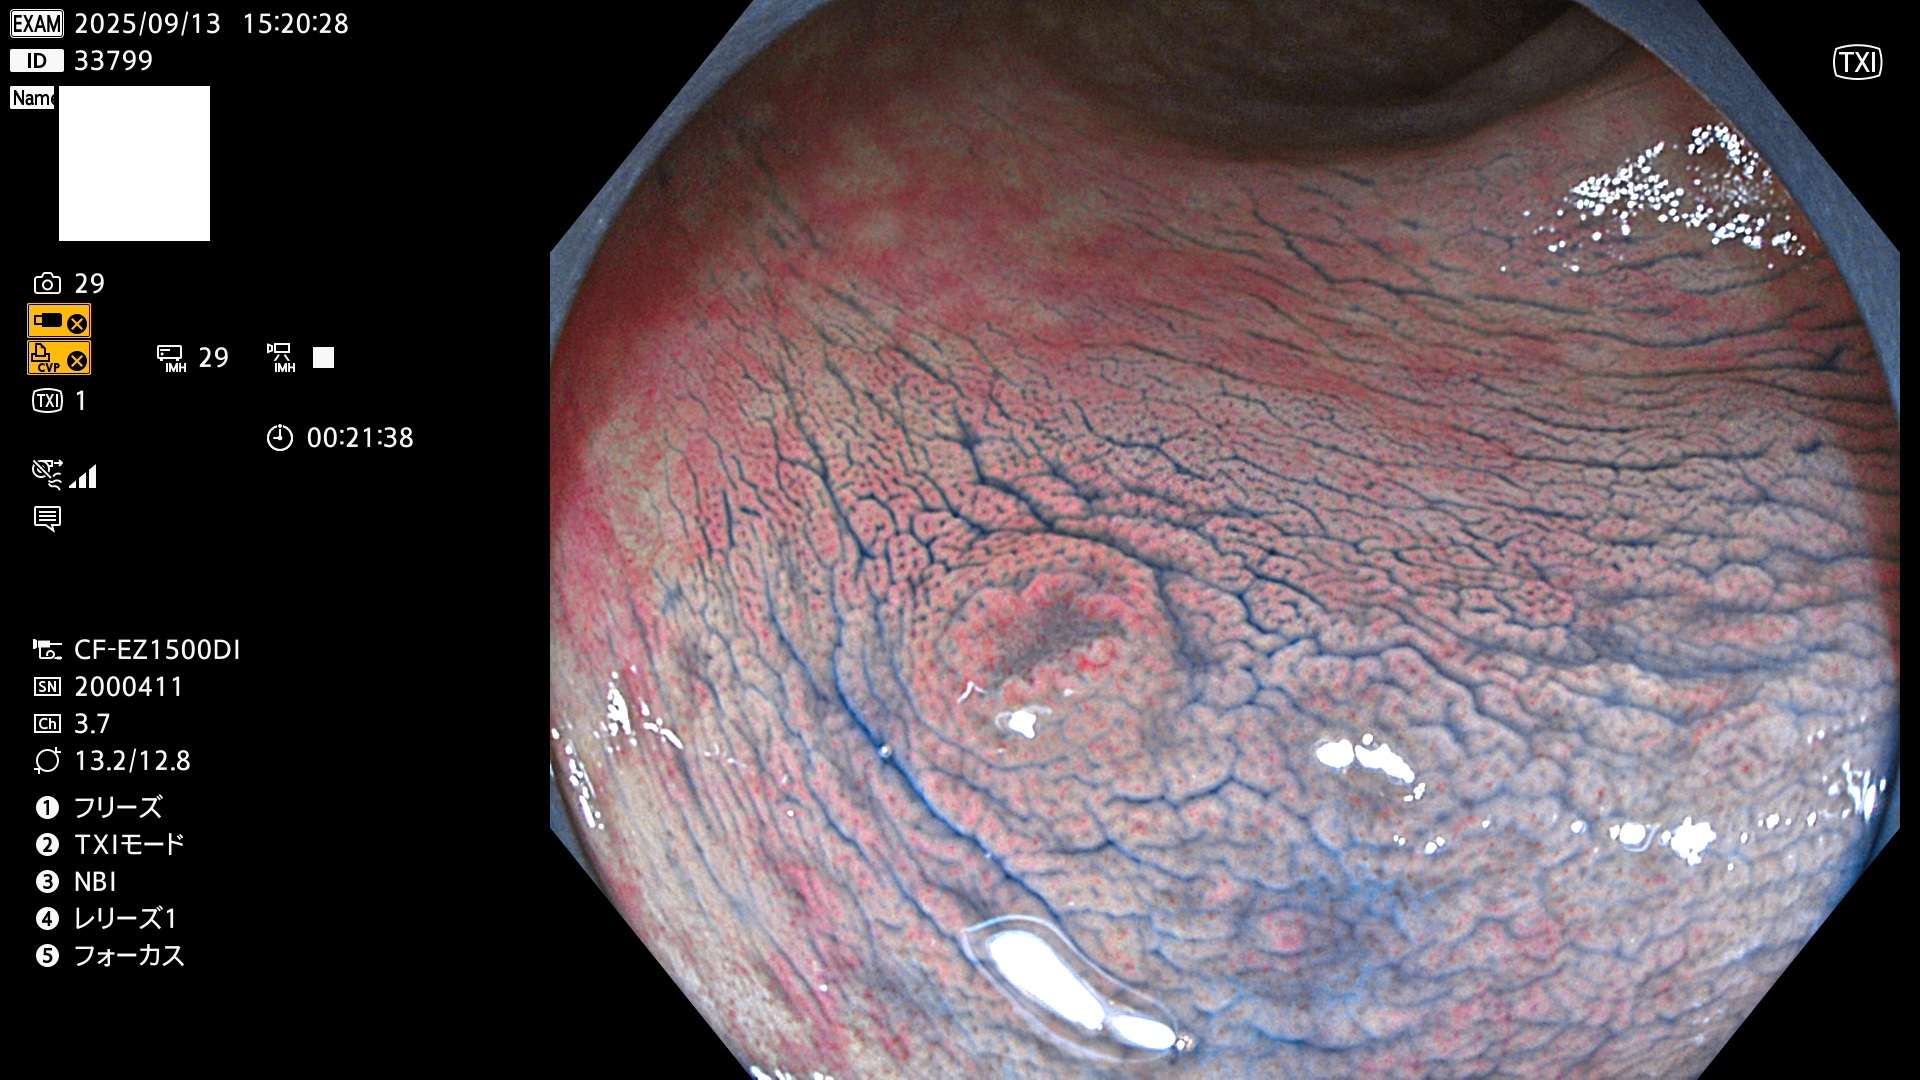

完全に平坦な物をUb、陥凹している物をUcと呼びます。Ubは認識が困難で、Ucはびらん(炎症)と紛らわしいために見落とされやすく、「内視鏡後・大腸癌」の原因になります。

専門的)Uc=De Novo癌? 内視鏡の解像度が低かった時代、このような説もありました。しかし今日の高精度内視鏡では良性の微小なUc型腺腫(APC遺伝子異常の腺腫)が日常的に見つかります。Ucこそが多段階発癌(Adenoma-Carcinoma Sequence)のMain Routeです。

毎週の検査(木・金・土・日)に発見されたUbとUc型・腺腫を、その週の日曜の夜にUPし1週間、提示します。

2025年9月11日〜9月14日の4日間(40件)7個 (Uc_ADR=7個/40人=18%)